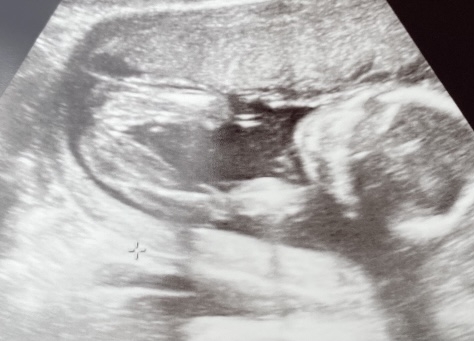

Könnt ihr zu diesem Bild meiner Freundin was sagen? der Nub hatte damals ein Mädchen gezeigt 17+5

Die Qualität ist leider etwas bescheiden

Könnt ihr zu diesem Bild meiner Freundin was sagen?